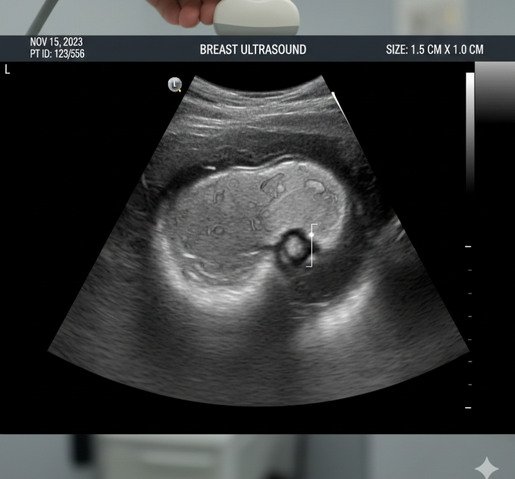

Ecografía Mamaria

La ecografía mamaria es un estudio no invasivo que permite evaluar el tejido mamario, analizando su estructura y la presencia de nódulos, quistes u otras alteraciones. Es una herramienta fundamental para el diagnóstico y seguimiento de patologías mamarias, especialmente como complemento de la mamografía o en pacientes jóvenes con tejido mamario denso.

En LUMA, la ecografía mamaria es realizada por profesionales especialistas en diagnóstico por imágenes, utilizando equipos de última generación y alta definición, que permiten obtener imágenes claras y precisas, optimizando la detección temprana y el diagnóstico confiable.